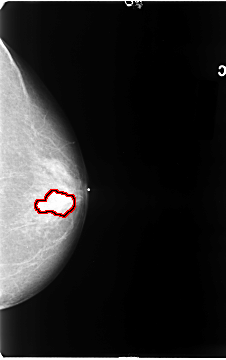

FILE: B_3088_1.LEFT_CC.OVERLAY

TOTAL_ABNORMALITIES 1

ABNORMALITY 1

LESION_TYPE MASS SHAPE LOBULATED MARGINS CIRCUMSCRIBED-OBSCURED-ILL_DEFINED

ASSESSMENT 3

SUBTLETY 4

PATHOLOGY MALIGNANT

TOTAL_OUTLINES 1

BOUNDARY